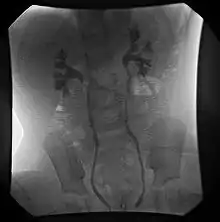

- Cystography

- Fluoroscopic voiding cystourethrogram (VCUG)

VCUG is the method of choice for grading and initial workup, while RNC is preferred for subsequent evaluations as there is less exposure to radiation. A high index of suspicion should be attached to any case where a child presents with a urinary tract infection, and anatomical causes should be excluded. A VCUG and abdominal ultrasound should be performed in these cases